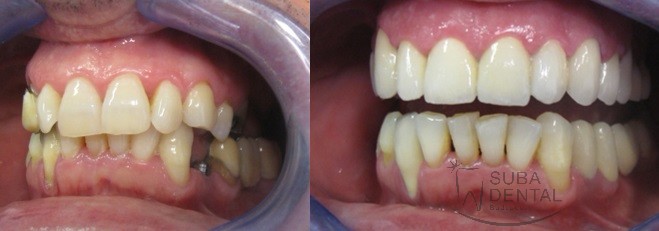

Before After